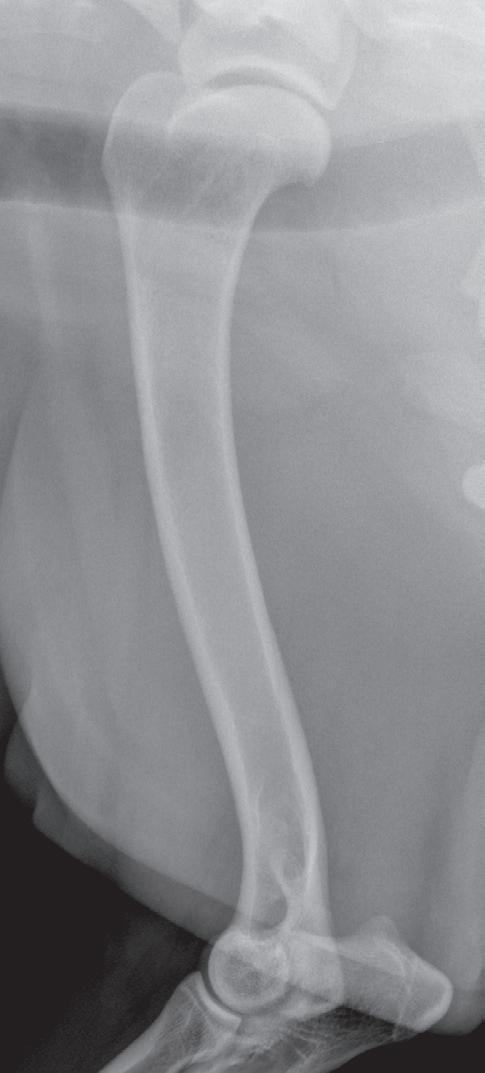

n As already noted, lateromedial or mediolateral images of extremities should be oriented with the proximal aspect of the limb at the top and the cranial or dorsal aspect of the limb heading to the examiner’s left (Figure 1-4). This orientation is correct regardless of whether the left or right limb has been imaged.

Figure 1-4. Correct orientation of lateral views of two extremities. A lateral view of a humerus (A) and a lateral view of a tarsus/pes (B) are shown here. Note the difference in directional terms depending on whether the part being imaged is above or below the tarsocrural or antebrachiocarpal joint.